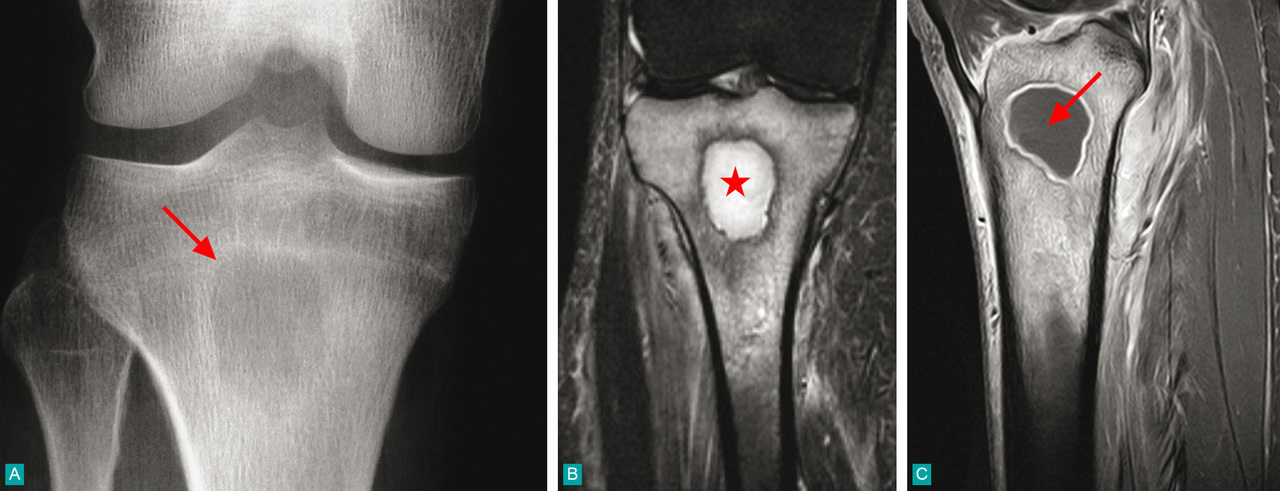

A. Radiographie standard de face : lacune métaphysaire bien limitée par un liseré de sclérose (flèche).B. Imagerie par résonance magnétique : coupe frontale en STIR, hypersignal intense de l'abcès centro-osseux (étoile).C. Après gadolinium, coupe sagittale en T1 avec suppression de graisse : rehaussement de la périphérie de l'abcès, le centre liquidien reste hypo-intense (flèche).